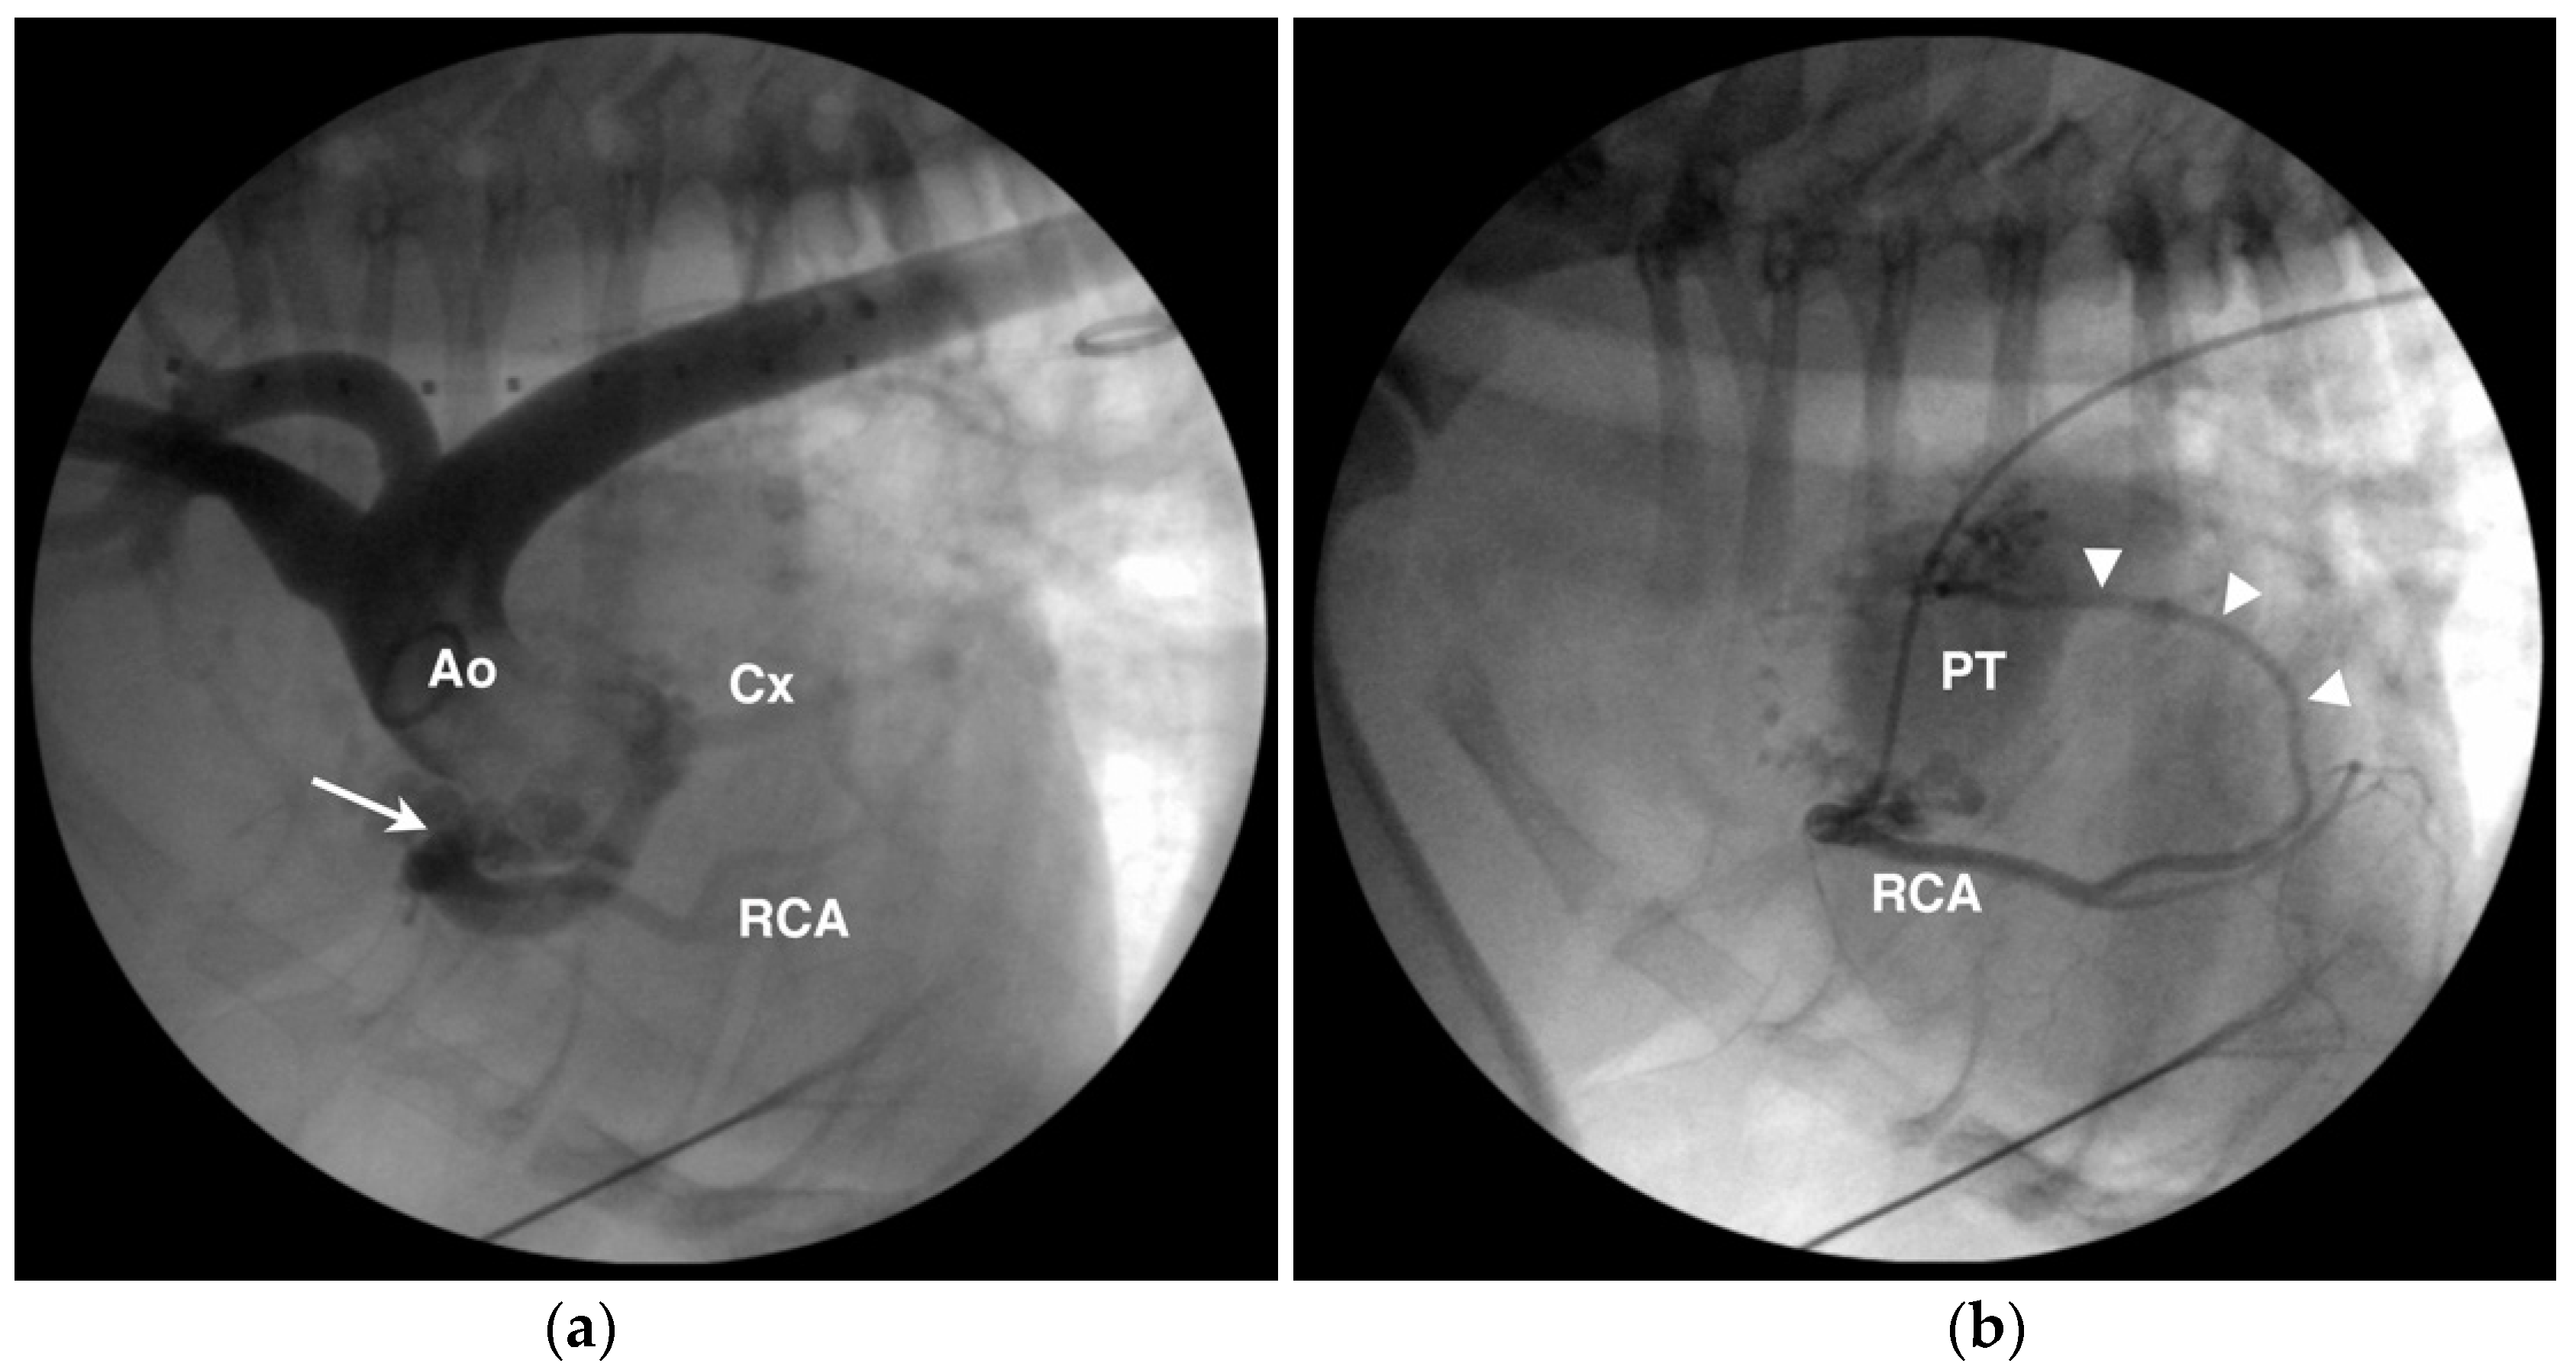

Coronary to pulmonary artery fistulae to the pulmonary circulation are occasionally observed in animals, most often in the author’s experience as part of a larger thoracic arteriovenous malformation [71], though isolated coronary to pulmonary arterial connections also occur (Figure 10).

Figure 10.

Angiographic images from an English bulldog with single right coronary ostium, aneurysmal dilation of the prepulmonary left coronary artery and circumflex branch (Cx), and coronary to pulmonary arterial fistulae/malformation. (a) The aortic root (Ao) injection shows the single right coronary ostium (arrow), aneurysmal dilation of the Cx, and a more normal diameter right coronary artery (RCA). (b) Selective right coronary angiogram from the same dog as in (a) showing one of several fistulous connections (arrowheads) from the RCA to the pulmonary trunk (PT).

6. Coronary Artery Aneurysm

Coronary artery aneuryms, also termed coronary artery ectasia, may be congenital or acquired. Reports in dogs have been in conjunction with subaortic stenosis [39], and fistulous vessels in published reports are often aneurysmal similar to that seen in Figure 9. An example of an aneurysmal RCA is provided in Figure 10 from an English bulldog with a single right coronary ostium, prepulmonary LCA, and fistulous connections to the pulmonary arterial circulation consistent with an arteriovenous malformation. The clinical significance of coronary artery aneurysms is uncertain and therapeutic intervention has not been reported in an animal. In humans, coronary artery aneurysms are typically acquired secondary to atherosclerotic, infectious, or connective tissue disease processes [72]. Therapy in people concentrates on limiting thromboembolic risk with antiplatelet and anticoagulant medications, implantation of covered stents, or surgical excision [72].